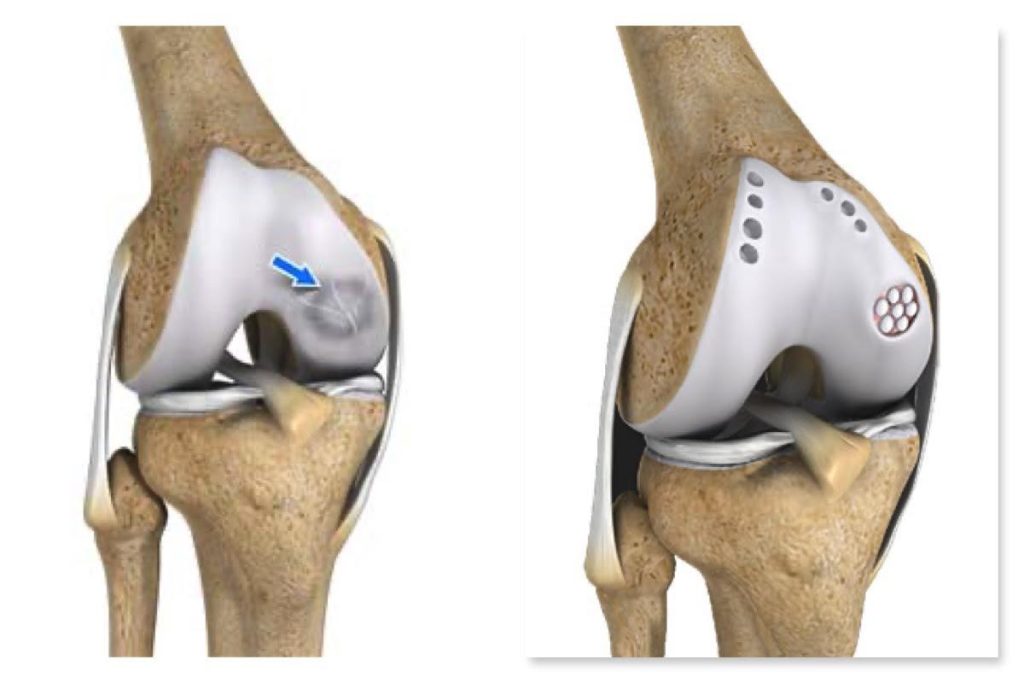

Joint Preservation Procedures

Joint preservation procedures are advanced medical and surgical techniques aimed at maintaining the natural joint structure, function, and mobility, thereby delaying or avoiding the need for joint replacement. These procedures...